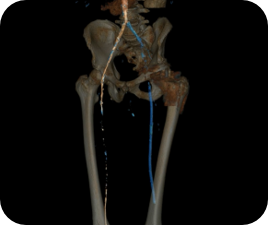

Évaluer